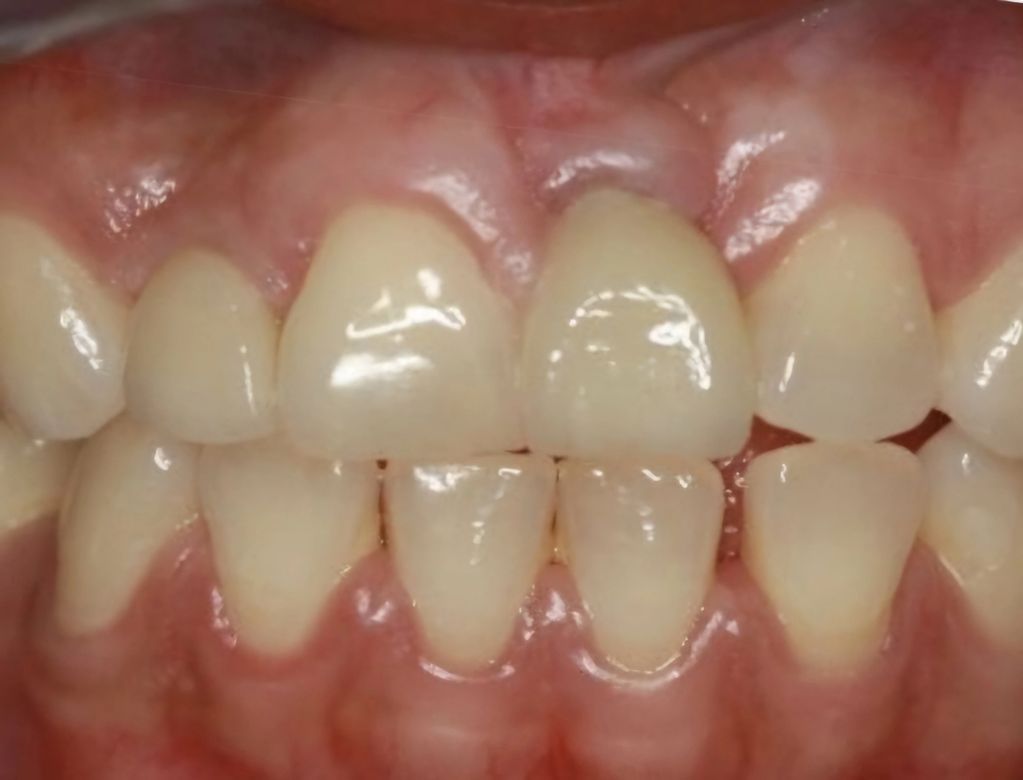

Observamos la foto clínica antes del procedimiento donde podemos apreciar la ausencia de los dientes 12 y 21, lo cual generaba mucha inseguridad en el paciente.

Observamos la foto inmediatamente al finalizar el procedimiento en el cual posicionamos 2 implantes corticobasales estratégicos mediante una cirugía minimamente invasiva, sin levantar colgajos de encía.

Al finalizar el procedimiento se tomaron los registros y se dejaron coronas acrílicas provisionales; 3 días después se instalaron definitivamente coronas en zirconio libres de metal. Tratamiento realizado en tan solo 72 horas.